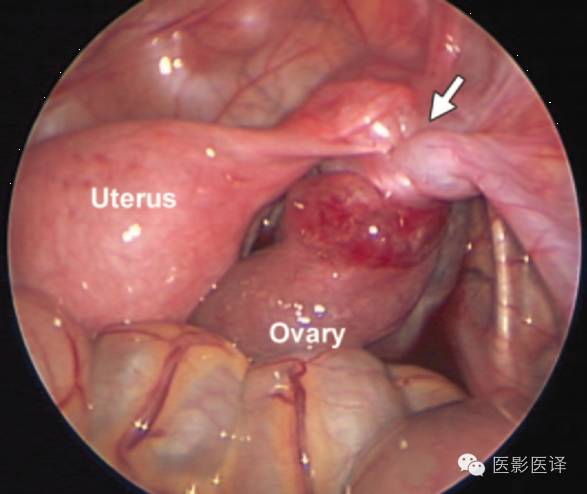

生后囊肿抽吸术可以减少扭转的几率,且争议较少,因为胎儿出生后诊断更加明确,手术并发症风险更小,因此生后囊肿抽吸术的“价值和安全性是明确的”。新生儿卵巢囊肿达4-5cm或是更大者,应该考虑卵巢抽吸术。生后卵巢囊肿最保守的治疗是观察一段时间,因为卵巢囊肿可能会自发缩小。生后新生儿应该每4-6周进行一次超声检查,直到卵巢囊肿消失、增大、出现症状或持续6个月无变化。手术指征通常包括复杂性、有症状、持续增大及超过6个月的囊肿。Zampieri等发现大于5cm的囊肿通常需要手术治疗。新生儿卵巢囊肿进行腹腔镜术后是可行且安全的。对于巨大卵巢囊肿,为了保存卵巢功能,应该行保守手术治疗,如囊肿剥除术或开窗术。如果观察期间发生卵巢扭转,可以尝试卵巢扭转矫正法来保存卵巢功能(图21)。如果扭转可能导致败血症或血流动力学不稳定,应该考虑行卵巢切除术和输卵管-卵巢切除术。